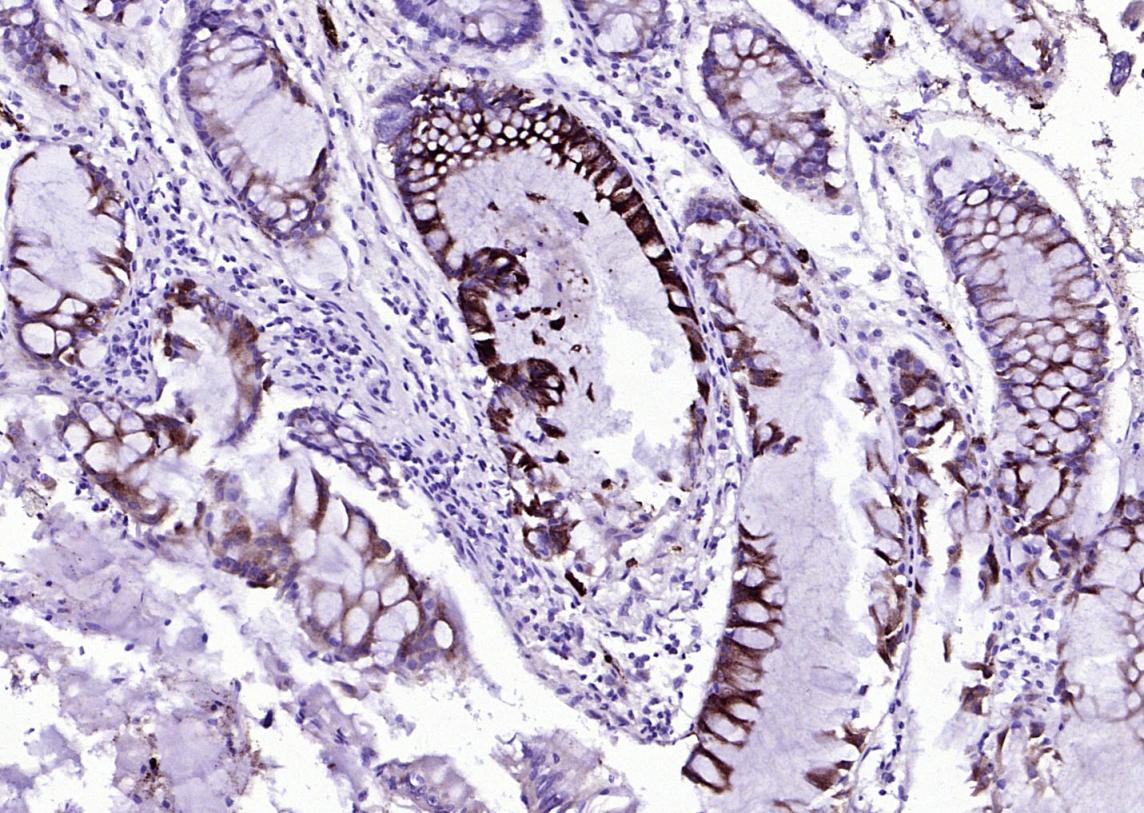

| 应用 | 已检合格种属 | 预测种属 | 推荐稀释比例 |

|---|---|---|---|

| IHC-P | Human | 1:100-500 | |

| IHC-F | Human | 1:100-500 | |

| IF | Human | 1:100-500 | |

| ELISA | Human | 1:5000-10000 |

交叉反应: Human